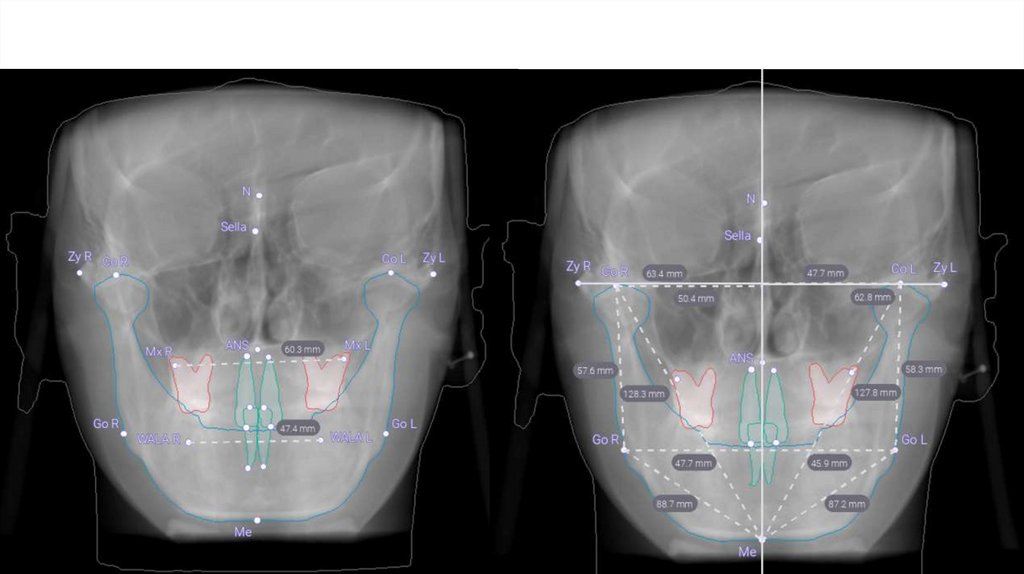

3. Симметричное расположение зрачковой линии, окклюзионная плоскость не имеет наклона

Правая сторона

Левая сторона